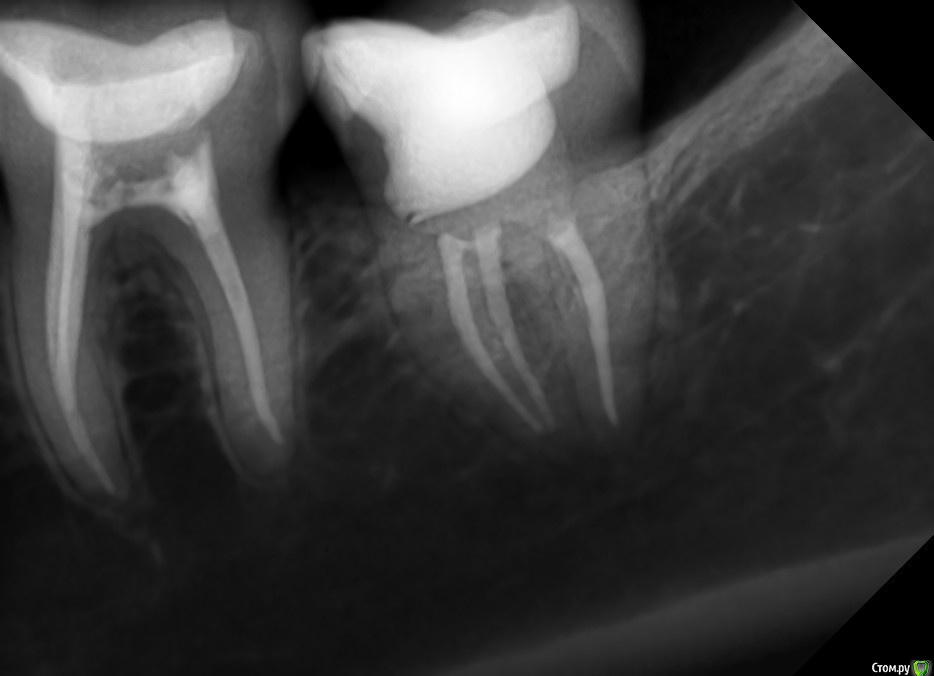

DA89 Опубликовано 8 мая, 2015 Поделиться Опубликовано 8 мая, 2015 Добрый деньПолгода назад была перелечена 7 снизу (был найден доп канал), положили кальций на 2 нед, неприятные ощущения прошли, запломбировали гутаперчей. Через 3 нед вновь появились неприятные ощущения (боль в ухе, подчелюстной лимфоузел увеличен и ощущения как будто зуб чешется, после того как пожую на него становится легче). Пропила курс настойки эхинацеи, стало легче, потом снова все вернулось. На сегодняшний день периодически боль в ухе, челюстном суставе, зуб как будто чешется, хочется на него накусить и увеличивается лимфоузел. Может дня 3 вообще ничего не беспокоить, либо беспокоить мин 30 в день и проходит, а может и весь день беспокоить. Доктор который его лечил сказал удалять. Есть ли смысл снова перелечивать каналы? Прикрепила снимки до лечения и спустя полгода Ссылка на комментарий

DA89 Опубликовано 14 мая, 2015 Автор Поделиться Опубликовано 14 мая, 2015 значит не совсем правильно чистите это косвенно говорит о наличии пародонтальной проблемы в этой области то есть болит без 3х недель полгода?да, уже полгода, судя по снимку, появились ли изменения за это время?Лечащий доктор сказал если чешется зуб и десна, это говорит об инфекции в корне...Другой стоматолог сказала что справиться с хроническим периодонтитом поможет лазерная физиотерапия. Есть ли смысл или это просто выкачивание денег? Ссылка на комментарий

Гарриевич Опубликовано 15 мая, 2015 Поделиться Опубликовано 15 мая, 2015 Другой стоматолог сказала что справиться с хроническим периодонтитом поможет лазерная физиотерапия не является лечебным мероприятием Лечащий доктор сказал если чешется зуб и десна, это говорит об инфекции в корне... не согласен появились ли изменения за это время? изменений не вижу, по снимку все в порядке зуб как будто чешется хочется на него накусить после того как пожую на него становится легче все это говорит за связочный аппарат, ищите проблему там Ссылка на комментарий